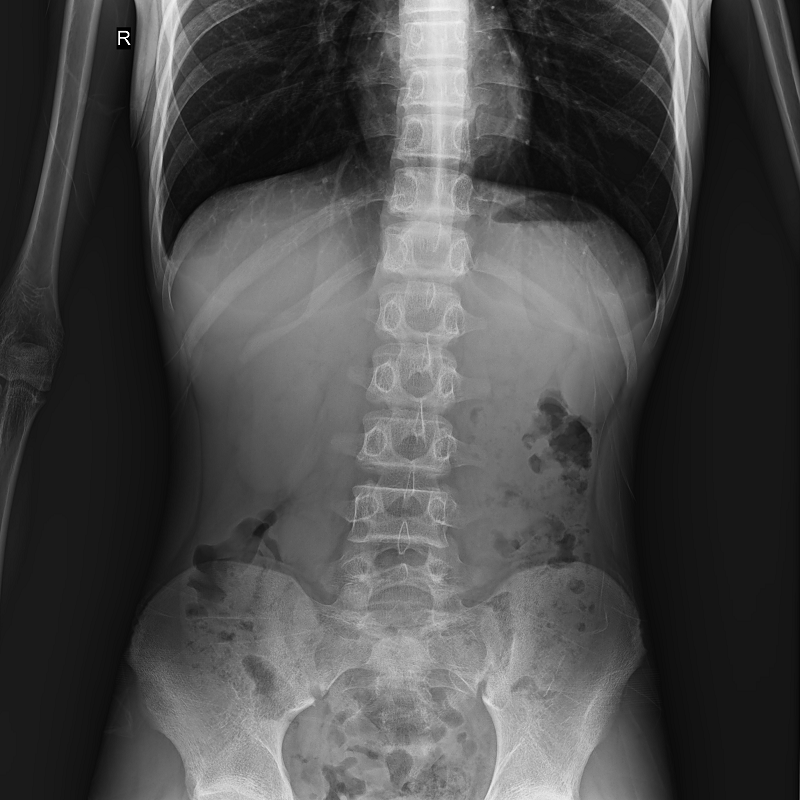

●呈現(xiàn)全下肢或全脊柱圖像

●在脊柱及下肢畸形矯正手術(shù)治療中,為術(shù)前方案制定和術(shù)后復查提供精準測量

●有效解決傳統(tǒng)X光片不能一次成像問題,為患者提供更加優(yōu)質(zhì)的醫(yī)療服務